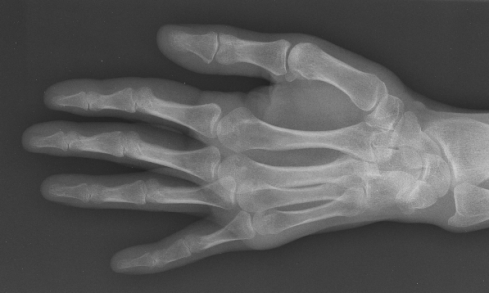

xray-2.png

Not to be confused with CTS, tendinitis is distinguished by pain. The under-side of the thumb and wrist can feel tender, achy, and over-worked. Bending the hand back sends lightning bolts through the forearm, forcing amateur yogis like me to attempt one-armed downward dogs—a practice fraught with perils of its own.

The symptoms of tendinitis are worse when the sun goes down.  In fact, it was in the middle of the night when I first realized that my hand and wrist—which had been sore for longer than I care to admit—were more than merely tired. I was jolted awake by an innocent mid-sleep stretch which caused not only pain, but also a horrible creaking in my forearm. It was as if the stretchy stuff in there had crumbled like an old rubber band.

Not a good feeling, people. Not good at all.